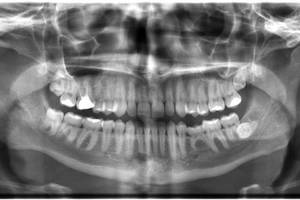

Your symptoms seem to indicate a chronic bacterial infection, and you maybe able to get rid of it if you look into your problems from this angle. If you have severe periodontitis, with receded gums and potentially infected alveoli, this is considered a nodule of disease, and means your immune system will be taxed with constantly fighting off low grade infections. This could easily open the way for more opportunistic infections, like the sinus and throat ills you are currently experiencing. Bacteria can easily enter your bloodstream, and your surrounding tissue (lie the walls of the sinus) can be irritated from being near the site of infection.

I would definitely recommend going to a dentist, and you may want to check yourself into a hospital as well, one that has a Periodontology or Oral Surgery ward.